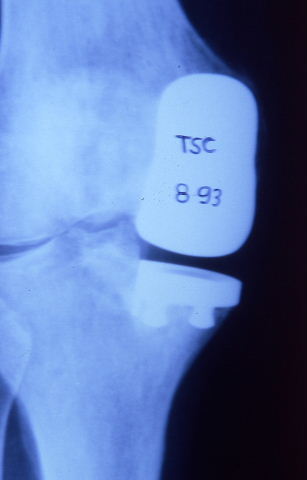

Prótesis completa de rodilla. Situación postquirúrgica.

Prótesis completa de rodilla. Situación postquirúrgica. Lateral.

Prótesis completa de rodilla.Lateral.

Prótesis completa de rodilla. Frontal.

Prótesis completa bilateral de rodillas.